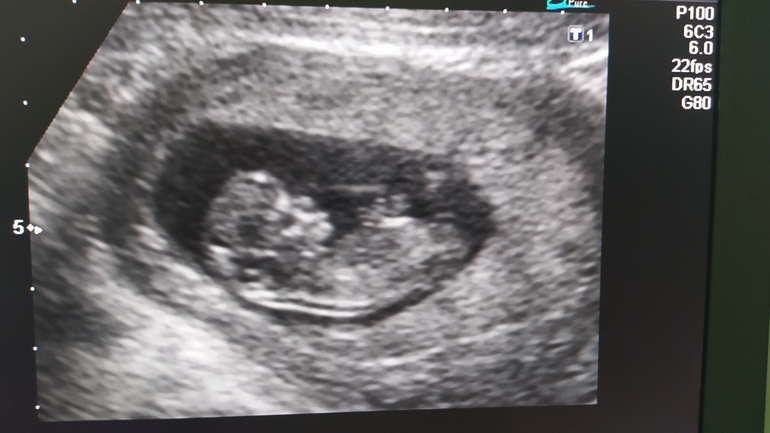

Фото прикрепляю с 13 и 17 недели ( может кто увидит пипиську?🤭)

13 недель